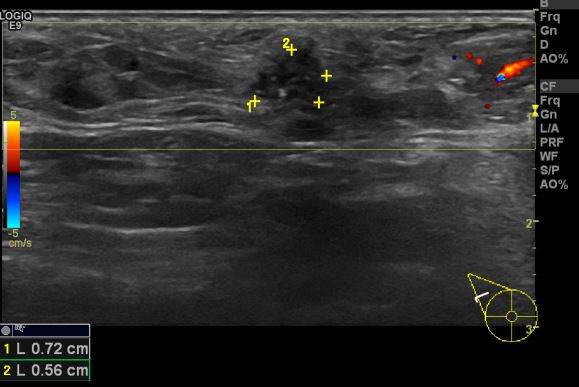

건강검진상 이상소견으로  내원하신 30대 여성분으로 우측 겨드랑이 부유방내에 만져지는 멍울 조직검사 시행하여 우측 침윤성 유관암 진단 되었습니다.